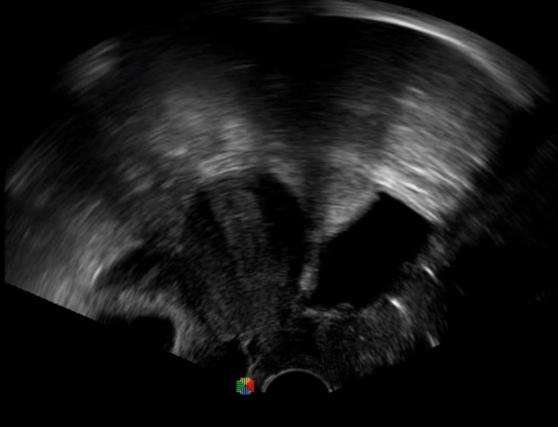

腹腔鏡超聲是超聲技術(shù)和腹腔鏡技術(shù)的融合,腹腔鏡超聲降低了對超聲探測深度的要求。由微小切口進(jìn)入手術(shù)部位,多角度彎曲可選擇,降低手術(shù)難度及風(fēng)險;與受檢組織器官直接接觸,有效避免氣體干擾。

應(yīng)用科室:麻醉科、手術(shù)室、普外科、泌尿外科、婦產(chǎn)科、腫瘤科、介入科等

腹腔鏡下 肝臟占位